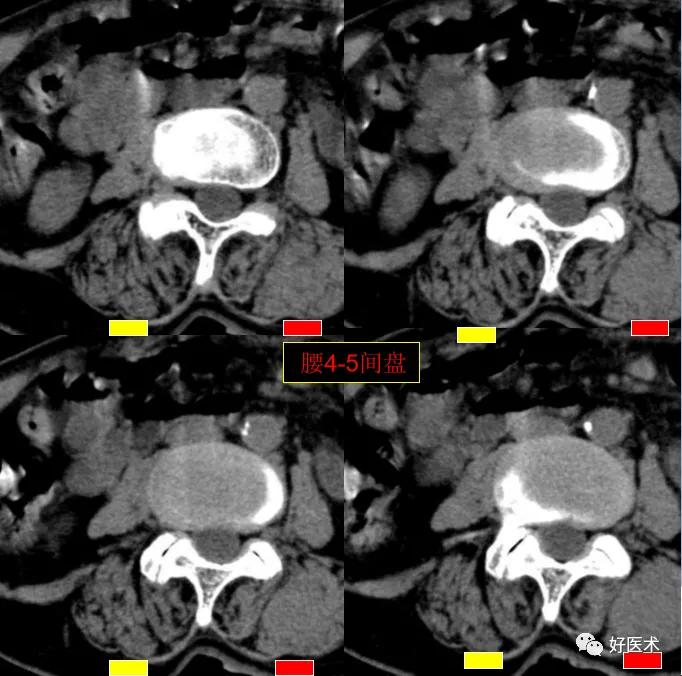

腰4-5间盘膨隆, 双侧椎小关节积气

发现了什么?左侧竖脊肌较右侧明显肿胀饱满, 肌间脂肪间隙消失!!